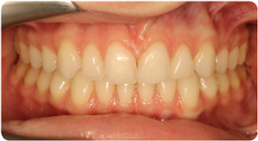

Each case shows the front view and an arch or side view, before and after BioLign Method-guided treatment.

All cases treated within 6–12 months.

Crowding with irregular gaps resolved into even alignment